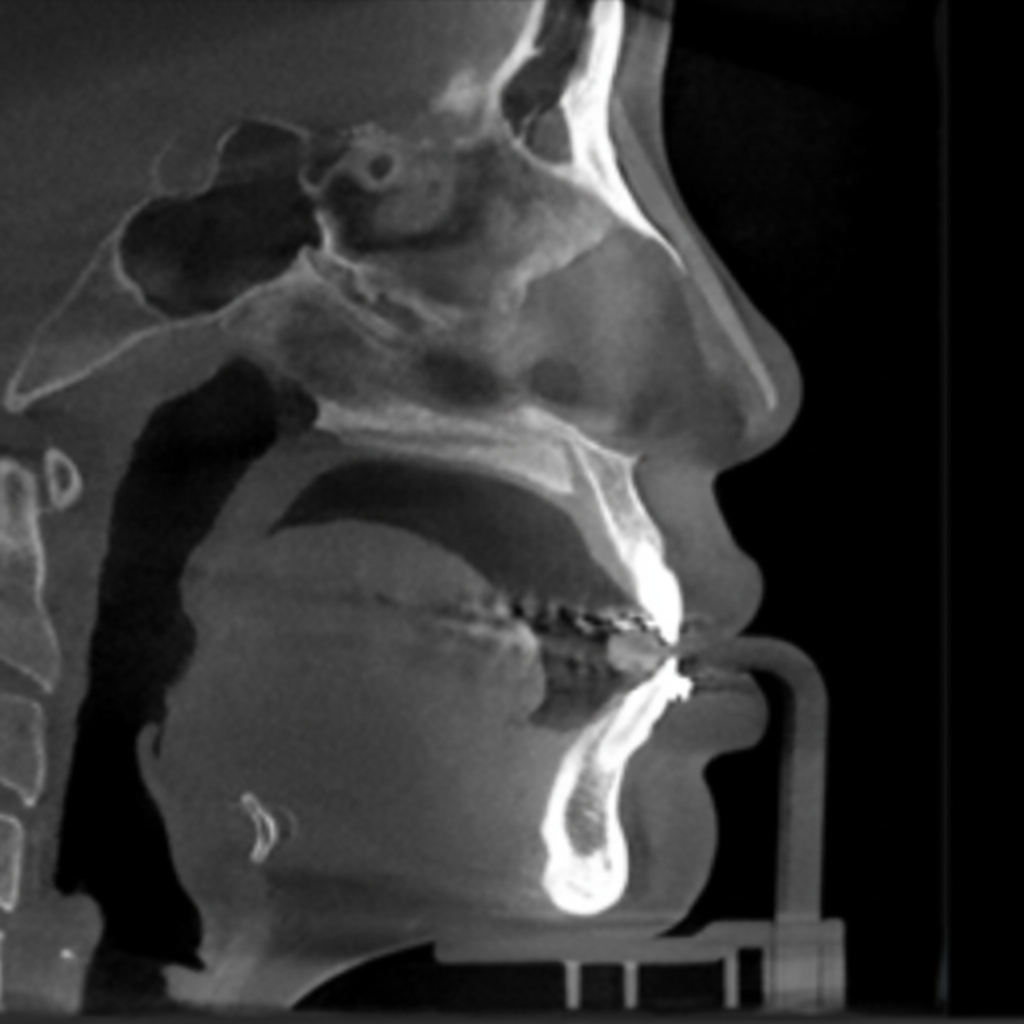

02 VIBE 수술 전 정밀진단

02

3D CT 분석에 의한 정밀진단

3D CT 분석을 통해 코뼈, 비중격, 연골길이, 내부변형 등 코 내부 상태에 대한 정확한 파악이 가능합니다.

코재수술의 경우 보형물의 위치, 고개기 대한 파악, 코골 연골과 변형 정도에 대한 예측을도 오차

다음 안정적인 결과를 도출합니다.

CT사진 1

CT사진 2

3D-CT 정밀진단

3D-CT

정밀진단

겉으로 보이지 않는

코 뼈, 비중격 연골,

비대칭 유무 확인